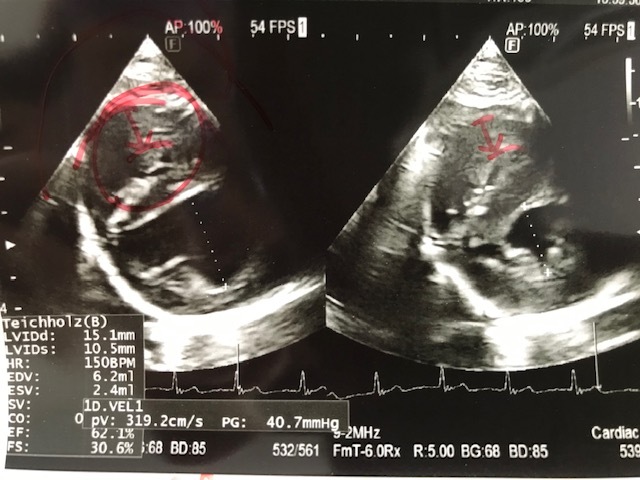

心臓の超音波検査:

三カ月前と比べて大きな変化がないとの事。

※赤丸が付いて所が心臓部(右心室・左心室)の所です。